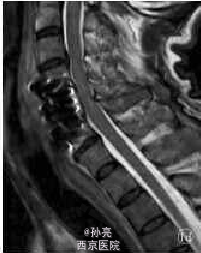

【一般资料】 患者,男,61岁。 【主诉】 因高处坠落致颈部疼痛2h余入院。 【查体】 C4-C6棘突压痛明显,活动受限,稍有肿胀,双上肢感觉麻木伴有痛觉过敏,双侧肱二头肌肌力Ⅳ级,双手握力下降,双下肢感觉活动可,肢端感觉血供可。入院时实验室检查均未见明显异常。MRI检查显示C3-C7椎间盘后突伴C4-C6平面椎管狭窄,颈髓受压,髓内见小片高信号影,颈椎退行性改变(图1a)。 【诊断】 ①颈椎病;②颈髓损伤。 【诊断治疗】 手术植入大小适中填满松质骨的钛网,再将长短合适的颈前路钢板系统通过螺丝钉固定于开槽减压区上下方椎体上。C形臂X线机透视证实钢板系统位置正确后,切口内置负压引流管,逐层缝合切口。手术顺利,出血约200ml。术后48h切口引流量约50ml,拔除引流管。术后复查X线片示内固定位置可(图1b,1c)。术后查体:双上肢感觉无麻木,双侧肱二头肌肌力Ⅳ级强,双手握力Ⅳ级,双下肢各肌群肌力Ⅴ级,感觉活动可。 术后第5天突发神志不清,躁动不安,查体:双上肢肌力Ⅲ级,双下肢肌力0级,病理反射未引出。急查头颅CT、血电解质、血气分析等均未发现明显异常,胸部CT示双肺下叶炎症伴两侧胸膜反应。经相关临床科室会诊后转入ICU监护,予抗感染,加强龙冲击等对症支持治疗。复查头颅MRI、DWI、MRA,胸腰椎MRI均未见明显异常,颈椎MRI示:C4-C6椎体内固定术后改变,颈髓受压,髓内见小片高信号影(图1d)。经外院脊柱外科专家会诊:颈髓受压影像考虑为内固定产生伪影所致。